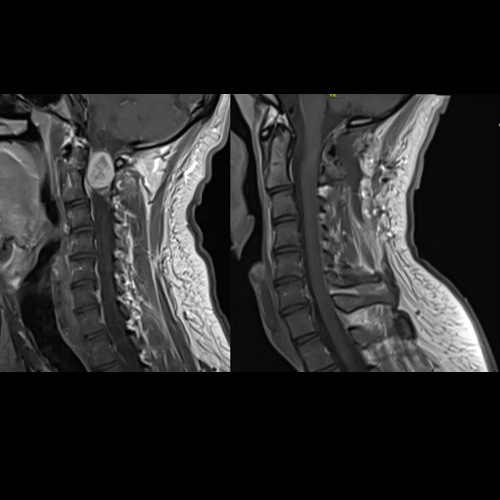

Spinal stenosis (Lumbar) Spinal stenosis (Cervical) Spinal stenosis (Thoracic) Lumbar Disc Herniation Spondylolisthesis Cervical Foraminal Stenosis Vertebroplasty Lumbar Fusion Anterior Cervical Fusion (ACDF) Posterior Cervical Fusion Thoracic Fusion Revision Lumbar Fusion Surgery Facet Joint Cyst Spinal Tumour Minimally Invasive Lumbar Fusion (XLIF) Minimally Invasive Lumbar Fusion (ALIF) Lumbar Fusion (TLIF) Thoraco-lumbar Fusion Lumbar Corpectomy Complex Lumbar Spine Surgery (Spino-pelvic fixation) Complex Cervical Spine Surgery Complex Thoracic Spine Surgery Occipito-cervical Fusion Minimally invasive surgery for thoracic disc herniation Other Related Topics